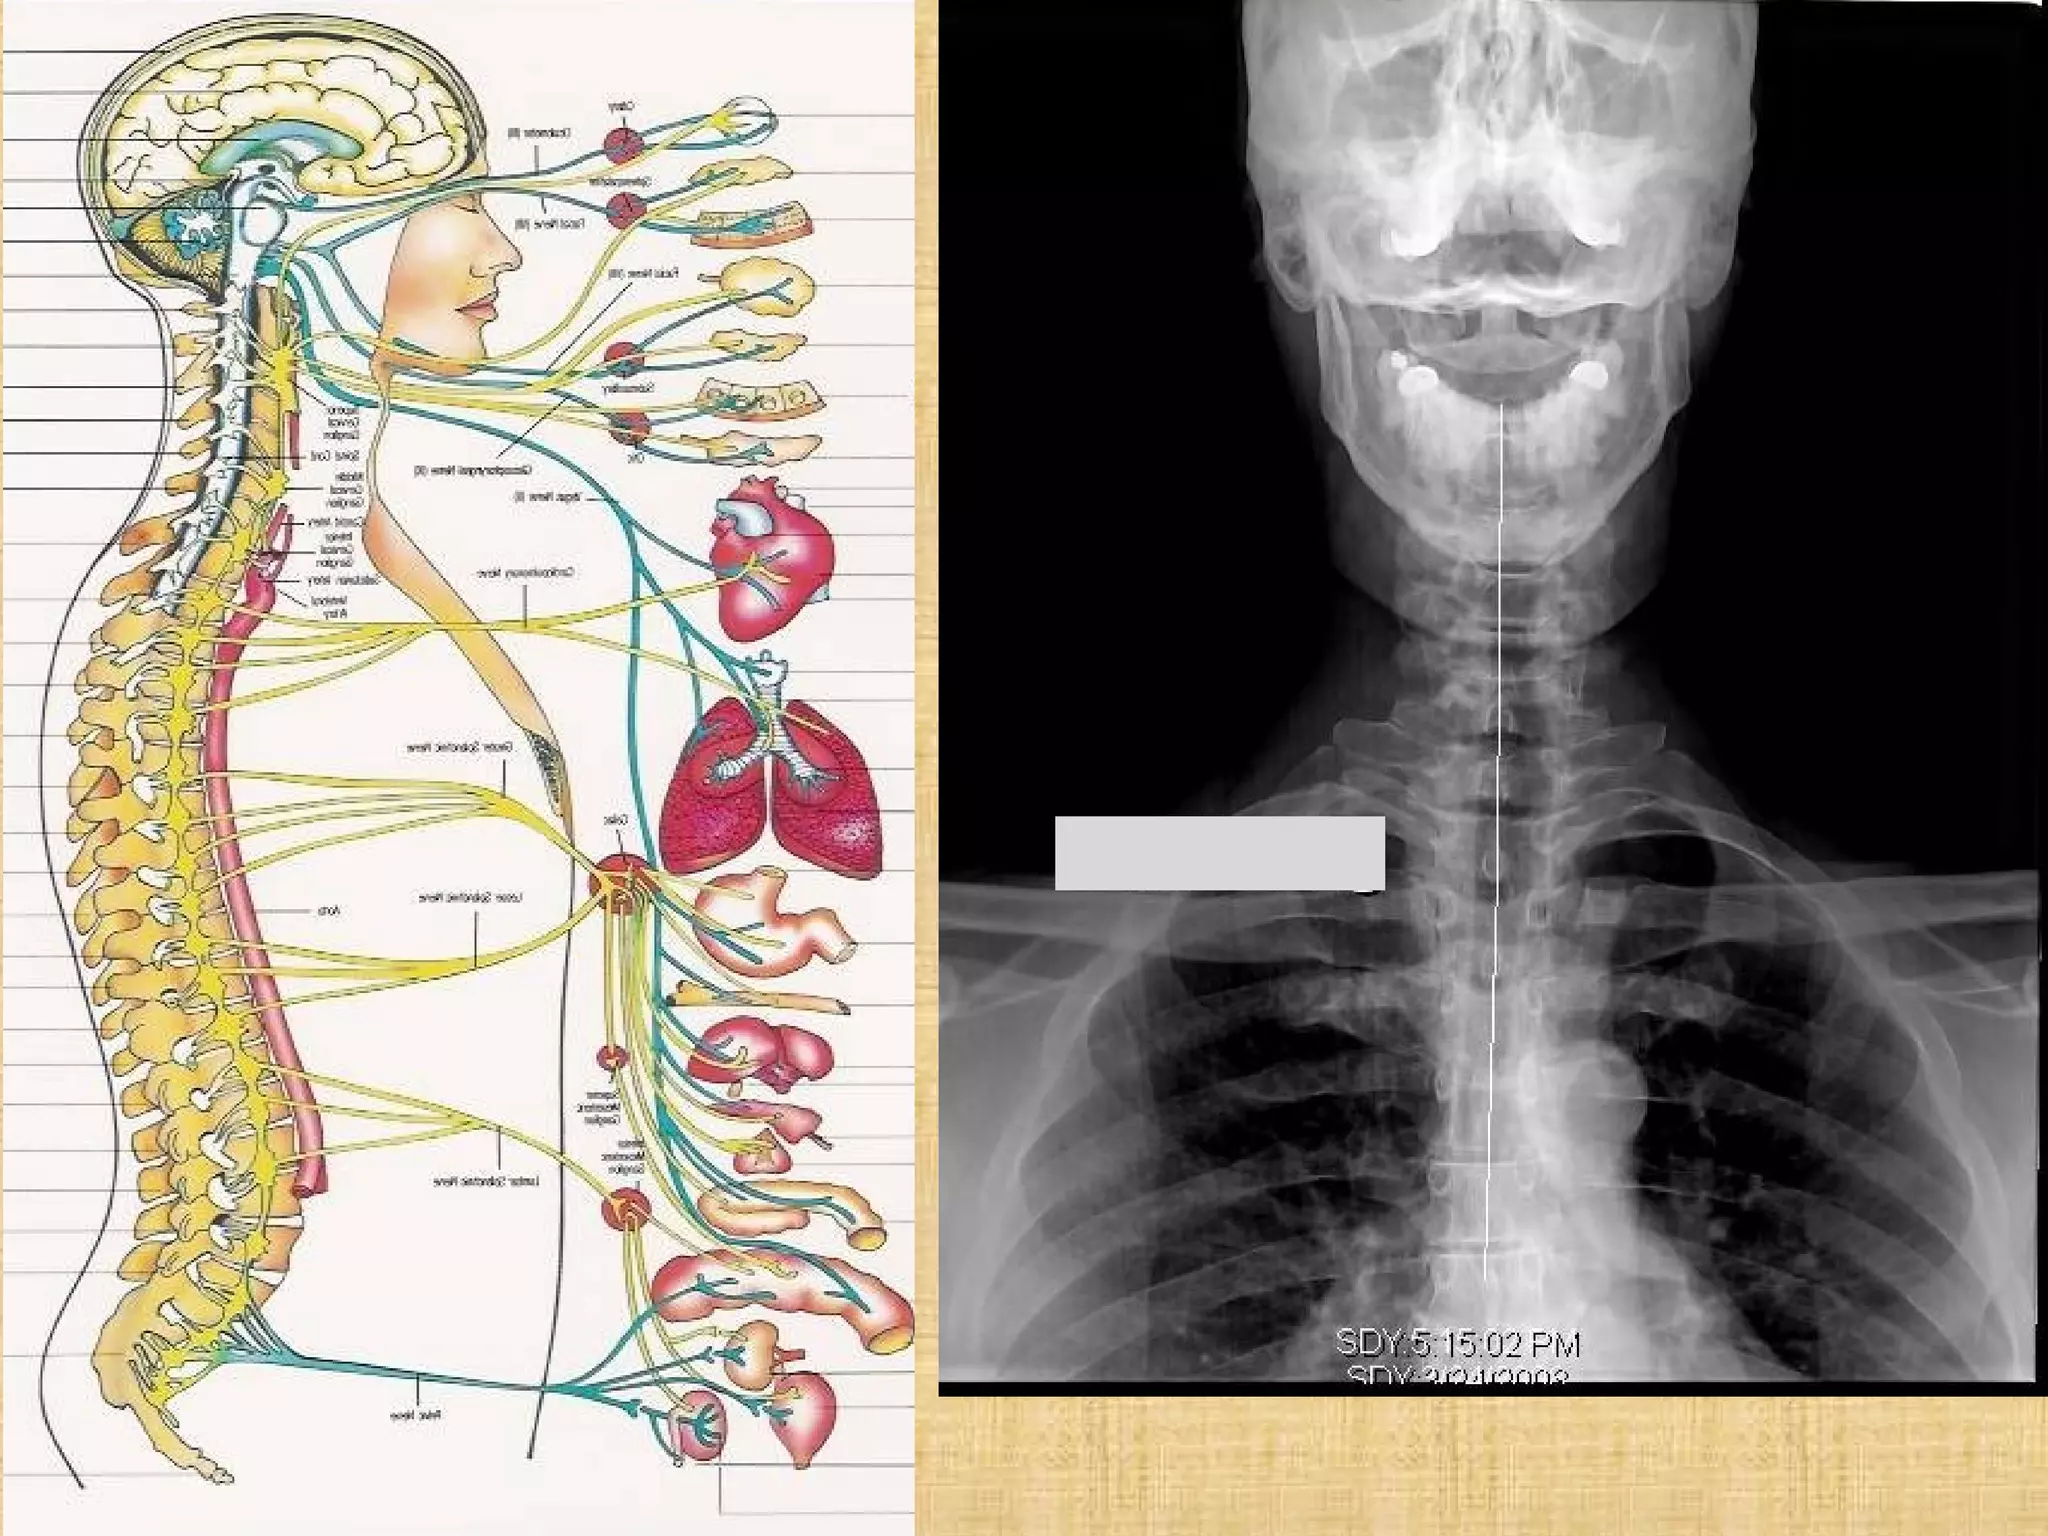

3 signals Cause dis-ease

1. Trauma. Misalignment of the spine can impede the

transmission of the nerve impulses

2. Toxicity. Toxins and poisons can distort the signal’s

information on its path between the nervous system

3.Thought Health is the nervous system’s ability to accurately

perceive environmental information and selectively engage

appropriate, life-sustaining behaviors.

If a mind misinterprets environmental signals and

generates an inappropriate response.

A thought could be enough to undermine an entire

system , misperceptions can be lethal.

The nervous system The nervous system

controls and coordinates all controls and coordinates all

functions of the body.  This functions of the body.  This

includes breathing, sleeping includes breathing, sleeping

digestion, and elimination.digestion, and elimination.

Gray’s Anatomy, pg. 4Gray’s Anatomy, pg. 4

3 signals Causedis-ease 1. Trauma. Misalignment of the spine can impede the transmission of the nerve impulses 2. Toxicity. Toxins and poisons can distort the signal’s information on its path between the nervous system 3.Thought Health is the nervous system’s ability to accurately perceive environmental information and selectively engage appropriate, life-sustaining behaviors. If a mind misinterprets environmental signals and generates an inappropriate response. A thought could be enough to undermine an entire system , misperceptions can be lethal.